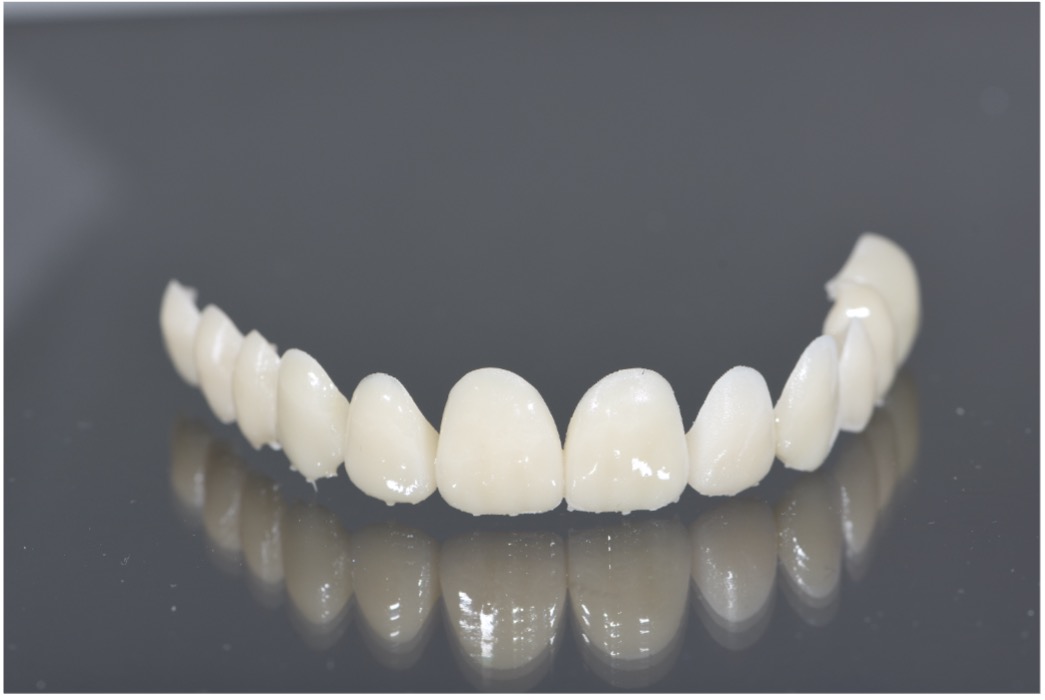

Once the digital design was approved, a physical mockup was created using resin for 3Dprinted materials. This mockup served as a test-drive for the proposed outcome, enabling real-time evaluation of the smile design in terms of esthetics, speech, and occlusion. The mockup was fitted in the clinic and reviewed from multiple angles, with special attention given to the patient’s reaction and comfort. Adjustments were made accordingly, allowing for refinements before any irreversible procedures were performed.

Step 4: Execution of the Final Restorative Plan

The final stage involved tooth preparation and the placement of definitive ceramic restorations. Using SmileFy digital smile design, the restorations were designed to replicate the previously approved mockup and accommodate the new gingival

architecture. These restorations were fabricated with high precision, ensuring excellent fit, esthetics, and durability. The bonding procedure was carried out with attention to Figure 19: 3D Printed Surgical Guide Try In Figure 20: Close Up Difference between 3D Printed Mockup and Initial Teeth Figure 21: During digital crown lengthening Figure 22: Post Op Intraoral Picture detail, followed by polishing to achieve a natural and vibrant finish. The completed smile